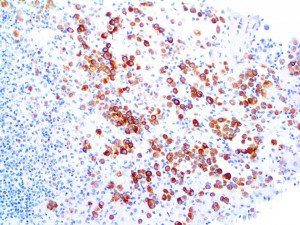

It is the ICU physician who is most likely to witness one of the deadliest manifestations of the abnormal immunological response, the cytokine storm syndrome (CSS). This response is also referred to by some as the cytokine release syndrome (CRS). CSS is characterized by continuous activation and expansion of macrophage and lymphocyte populations, which secrete large amounts of cytokines, causing the cytokine storm. This massive cytokine release is akin to hemophagocytic lymphohistiocytosis (HLH) disease, a syndrome characterized by initial unchecked and persistent activation of cytotoxic T lymphocytes and NK cells.

Clinical and laboratory manifestations of HLH include fever, enlarged liver and/or spleen, neurologic dysfunction, coagulopathy, liver dysfunction, cytopenias (i.e., low levels of erythrocytes, leukocytes, and/or platelets), hypertriglyceridemia, hyperferritinemia, hemophagocytosis, and eventually diminished NK cell activity as the immune system becomes progressively paralyzed. HLH can be familial (primary HLH) or secondary to another disease process (sHLH), such as rheumatic disease, in which it is referred to as macrophage activation syndrome (MAS, characterized by elevated ferritin).